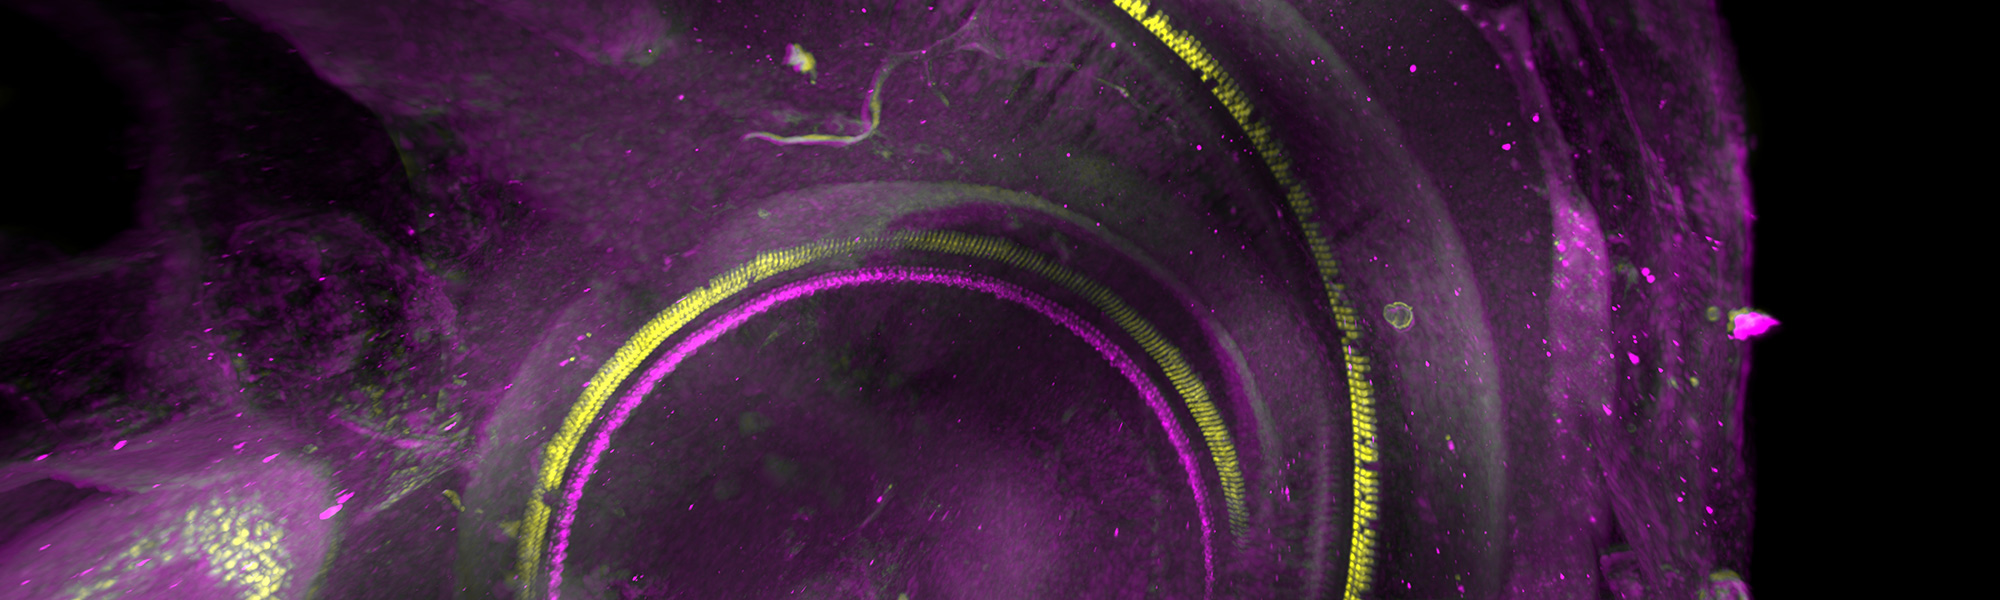

Regeneracja komórek włoskowatych w uchu wewnętrznym budzi nadzieje na naturalną naprawę słuchu po uszkodzeniach akustycznych czy starzeniowych. Te delikatne struktury, zlokalizowane w ślimaku, przekształcają fale dźwiękowe w sygnały nerwowe dzięki stereociliom – mikrowłoskom reagującym na drgania. W organizmach ptaków i ryb komórki te regenerują się spontanicznie, zastępując utracone egzemplarze nowymi. U ssaków, w tym człowieka, proces ten jest mocno ograniczony w wieku dorosłym, choć istnieją mechanizmy wsparcia. Komórki podporowe w narządzie Cortiego mogą proliferować i różnicować się w nowe komórki włoskowate pod wpływem określonych sygnałów molekularnych. Badania wskazują na rolę genów np. Atoh1, które aktywują ścieżki transkrypcyjne potrzebne do odbudowy. Czy jednak pełna regeneracja słuchu poprzez samonaprawę jest realna? Specjaliści podkreślają, że urazy głośnym hałasem prowadzą do apoptozy komórek włoskowatych, co uniemożliwia spontaniczną odnowę bez interwencji.

W ślimaku ucha wewnętrznego komórki włoskowate dzielą się na wewnętrzne i zewnętrzne, przy czym te ostatnie są szczególnie podatne na uszkodzenia (np. przez leki ototoksyczne). Mechanizmy naprawy obejmują proliferację komórek podporowych, które w warunkach laboratoryjnych przekształcają się w poręczne hair cells. Stereocilia spełniają podstawową kwestię w detekcji dźwiękuich uszkodzenie powoduje niedosłuch neurosensoryczny. Wielu badaczy wskazuje na potencjał terapii genowych, stymulujących ekspresję kwestii wzrostu jak FGF czy Notch. Pytanie brzmi: jak komórki włoskowate ucha wewnętrznego mogą naprawiać się same w codziennych warunkach? Podstawowe mechanizmy: